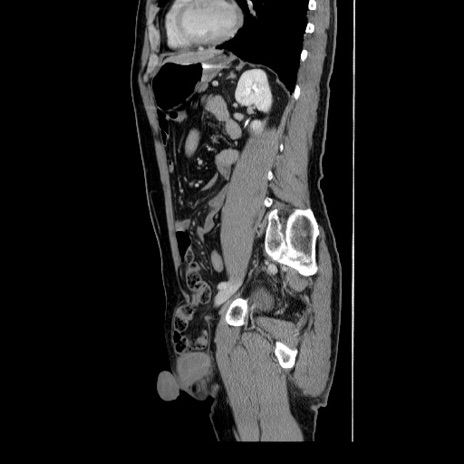

症例34(矢状断像)

【症例】60歳代 男性

【主訴】右鼠径部膨隆

【現病歴】1年程前より右鼠径部膨隆あり。自己にて還納可能だったため放置していた。3時間前より右鼠径部の脱出を認め、還納困難となり受診。

【既往歴】高血圧

【身体所見】右鼠径部に小児頭大の膨隆あり。弾性硬であり、用手還納は困難。左鼠径部にも膨隆を認める。脱出はなし。